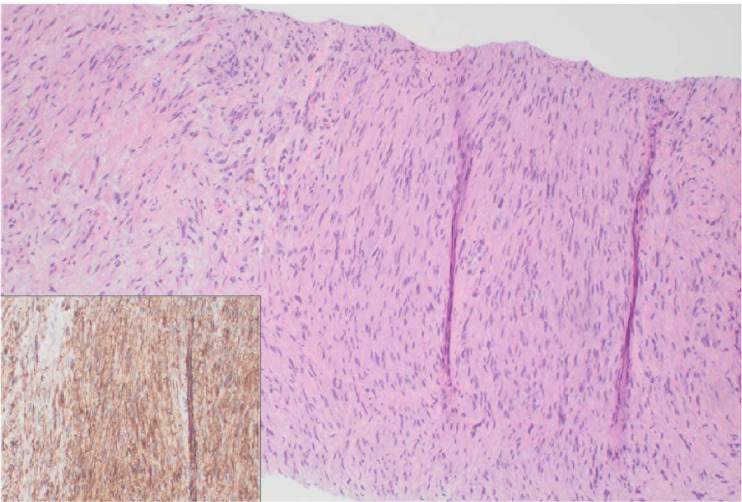

白血病肿块是血液恶性肿瘤患者的一种已知并发症。我们在此介绍一例新近确诊的 B 型急性淋巴细胞白血病(B-ALL)患者,该患者出现多个部位的髓外受累,包括前纵隔肿块。尽管接受了多剂细胞毒治疗,但肿块仍持续存在。在本报告中,我们总结了有关 B-ALL 纵隔肿块的文献,并说明白血病患者的此类肿块可能有令人惊讶的病因,与原发疾病无关。

Leukemic masses are a known complication in patients with hematologic malignancies. Here we present a case regarding a patient with recently diagnosed B-acute lymphoblastic leukemia (B-ALL) who presented with multiple sites of extramedullary involvement including an anterior mediastinal mass. This mass persisted despite multiple rounds of multiagent cytotoxic therapy. In this report, we summarize the literature regarding mediastinal masses in the setting of B-ALL and illustrate that such masses in patients with leukemias may have surprising etiology, separate from the primary disease.